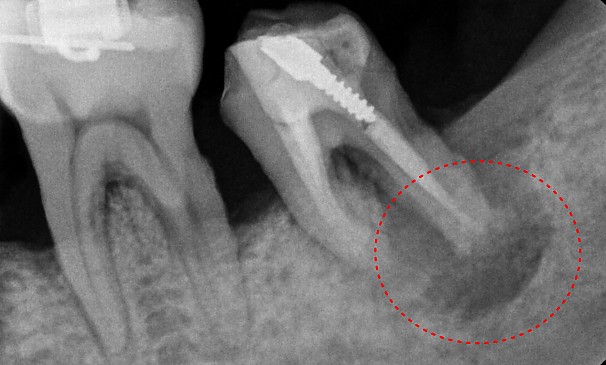

윤OO님 전후사진 | 치료 기간 : 6주

치료 후